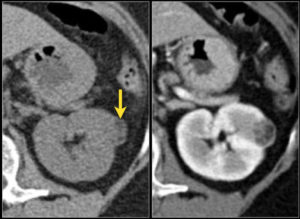

Ультразвуковое обследование уточнит размеры, локализацию, структуру патологии, наличие метастазов. Часто под контролем УЗИ в условиях операционной проводится взятие биоптата. Компьютерная и магнитно-резонансная томография также представят информацию о распространенности новообразования, поражении близлежащих органов, наличии тромбоза вен.

Иногда перед обследованием пациенту внутривенно вводится контраст. Опухолевые клетки обладают свойством накапливать вещества, и это позволяет определить даже микроскопические очаги поражения.

Для диагностики распространенности процесса показано выполнение КТ, МРТ, рентгенографии и рентгеноскопии легких, УЗ печени и забрюшинных лимфоузлов, рентгенографии и сцинтиграфии костей скелета.